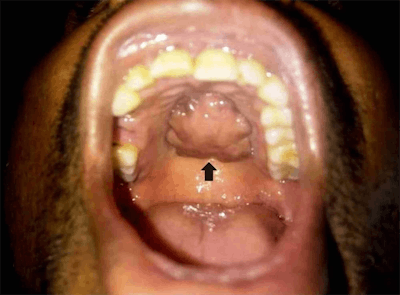

An exam of the man's mouth showed that his oral hygiene was poor and that a 4 x 2.5-cm, well-defined, firm, immobile mass was clearly visible on his hard palate, according to the authors.

A CT scan of the face revealed a well-defined, lobulated soft-tissue lesion with a peripheral rim of calcification along the inferior aspect of the hard palate. It did not appear to invade any adjacent structure.